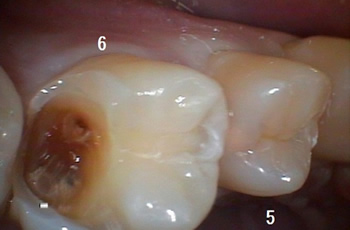

この場合は白っぽいところは崩壊寸前の状態でしたので、、、

少し削りますと、ズボッ、、、ボロボロと壁が壊れまして、、、

薄かわ一枚というか、玉子の殻の中が空洞なような感じで中はエライことに、、、

この状態で口腔内カメラで撮影して「茶色のところは全部虫歯ですよ!」

と説明すると、たいていは理解して下さります!!!

明らかだけに!!! |